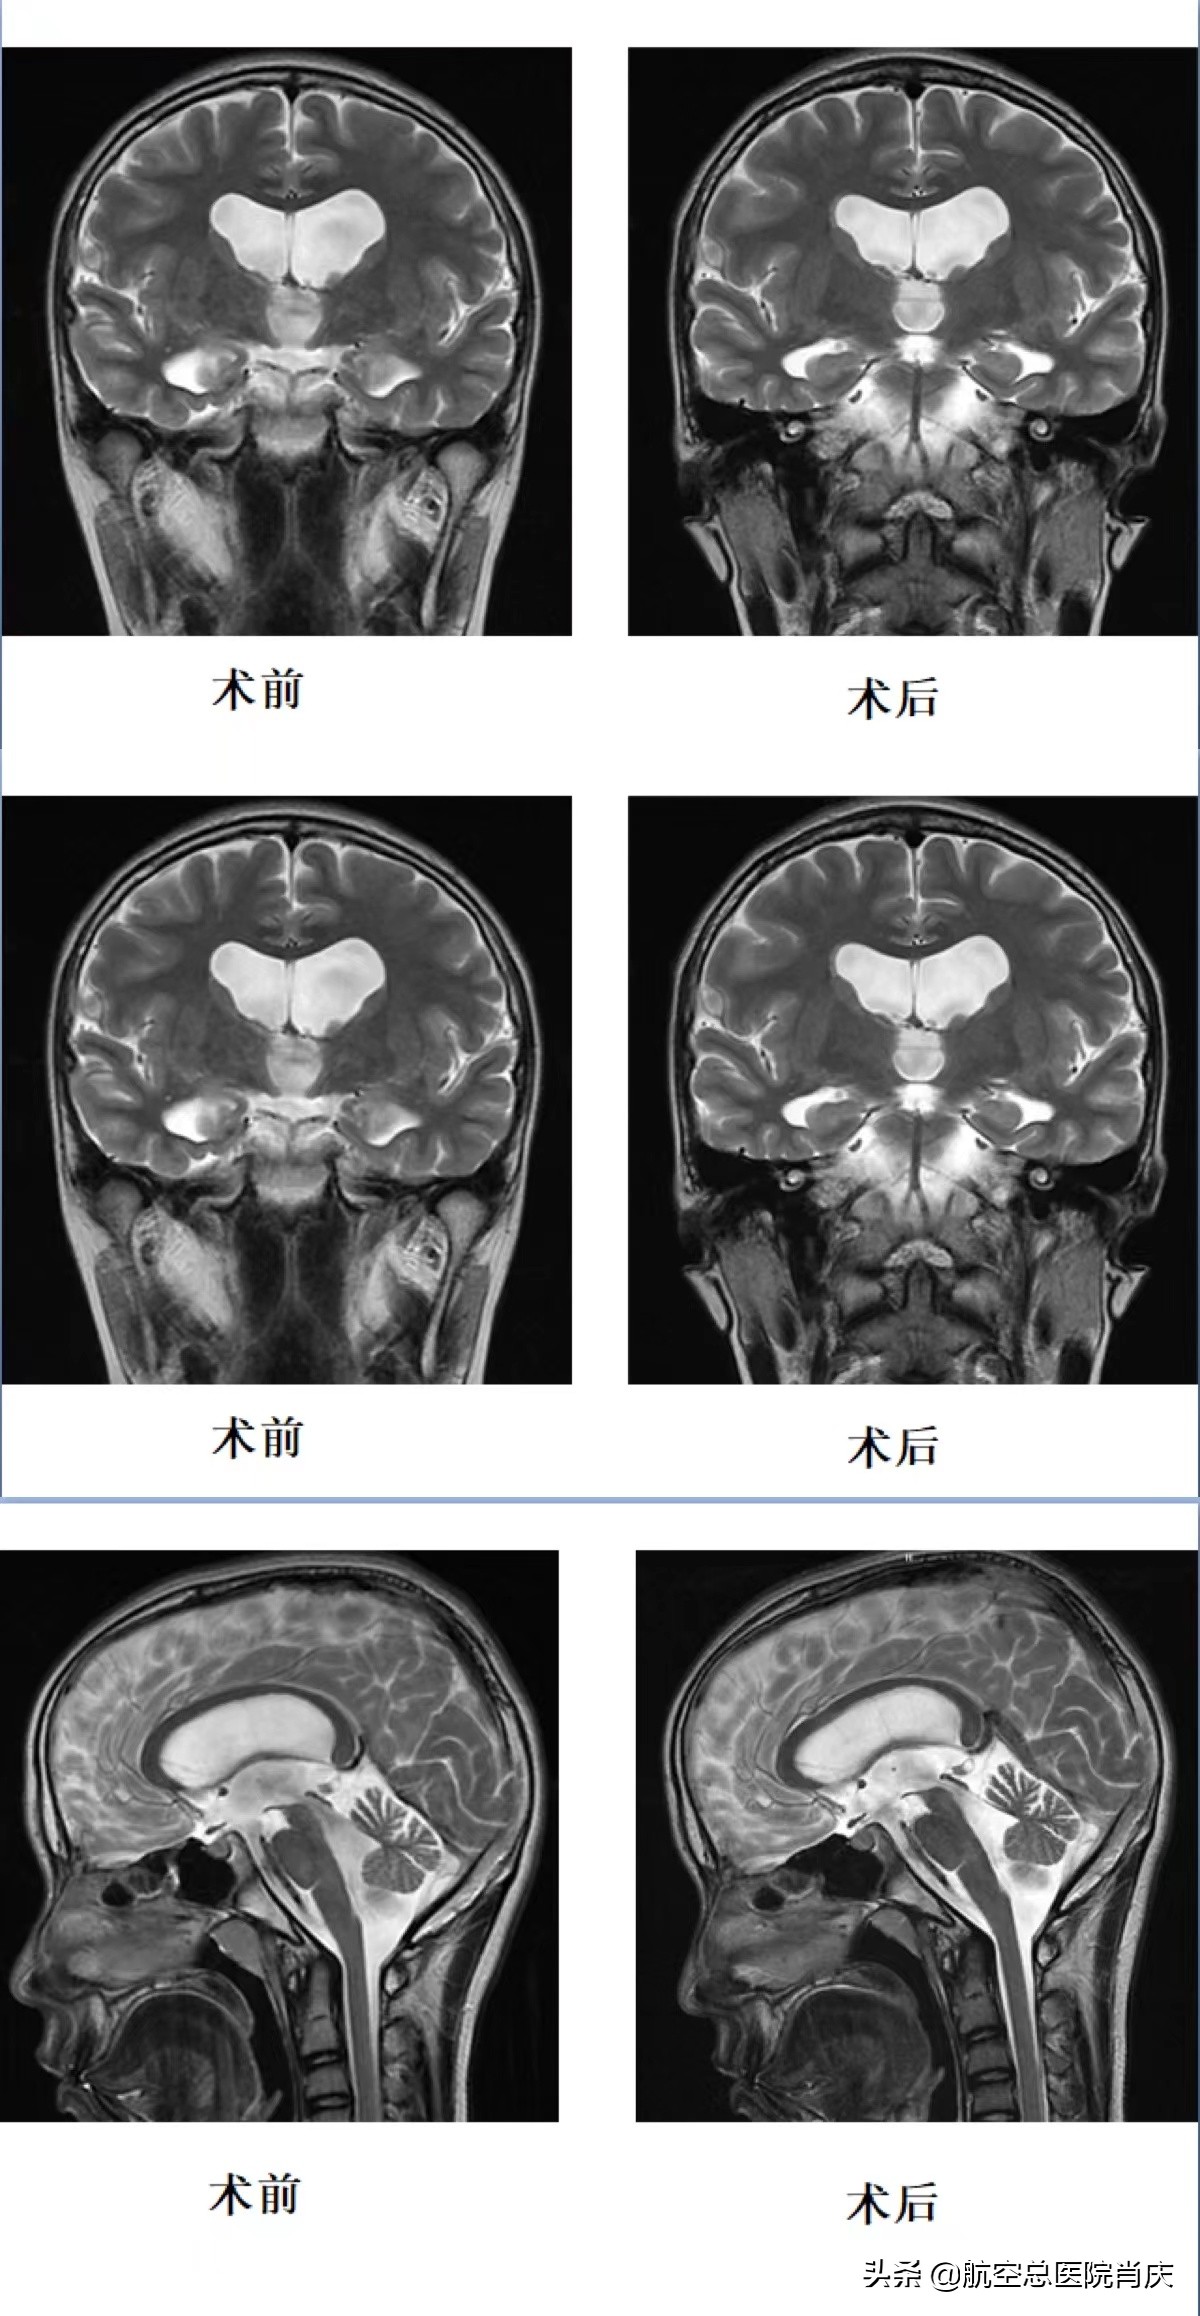

小孙入院六天后在全麻下进行了神经内镜下第三脑室底造瘘术,行第三脑室底造瘘后见基底动脉搏动可,并松解基底池内粘连,手术非常顺利成功。术后经过一系列治疗调养,各种症状逐渐减轻消失。头颅MRI复查见第三脑室底瘘口处流空影明显,小孙的头也不再痛了,已经可以出院休养。从四月中旬入院,到五月上旬出院,肖主任和其团队凭借多年的经验和精湛的医术以及细致耐心的态度,解决了患者多年的病痛折磨,为小患者今后的人生开启了更多可能和希望。